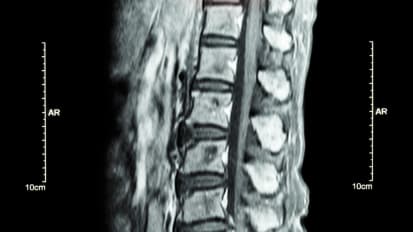

Johns Hopkins neurosurgeon Daniel Lubelski discusses the importance of pathology, biomarkers and genetics in treatment of spine tumors. Immunotherapy and targeted therapies are used to approach tumors that have been bio-banked and gene-sequenced, resulting in a tailored treatment plan. This, combined with advanced medical and surgical options, is leading to the best possible outcomes for patients with spine tumors.